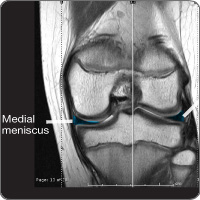

Meniscal tear

cond-menisThe menisci are two C-shaped fibrocartilage structures that serve as padding and separate the two bones of the knee joint, the femur (thigh bone) and tibia (lower leg/shin bone). The menisci disperse 30-55 percent of the forces that impact the knee joint. The menisci also provide stability, cushioning and aid in joint lubrication. The medial (inside) meniscus is injured four times as often as the lateral (outside) meniscus.